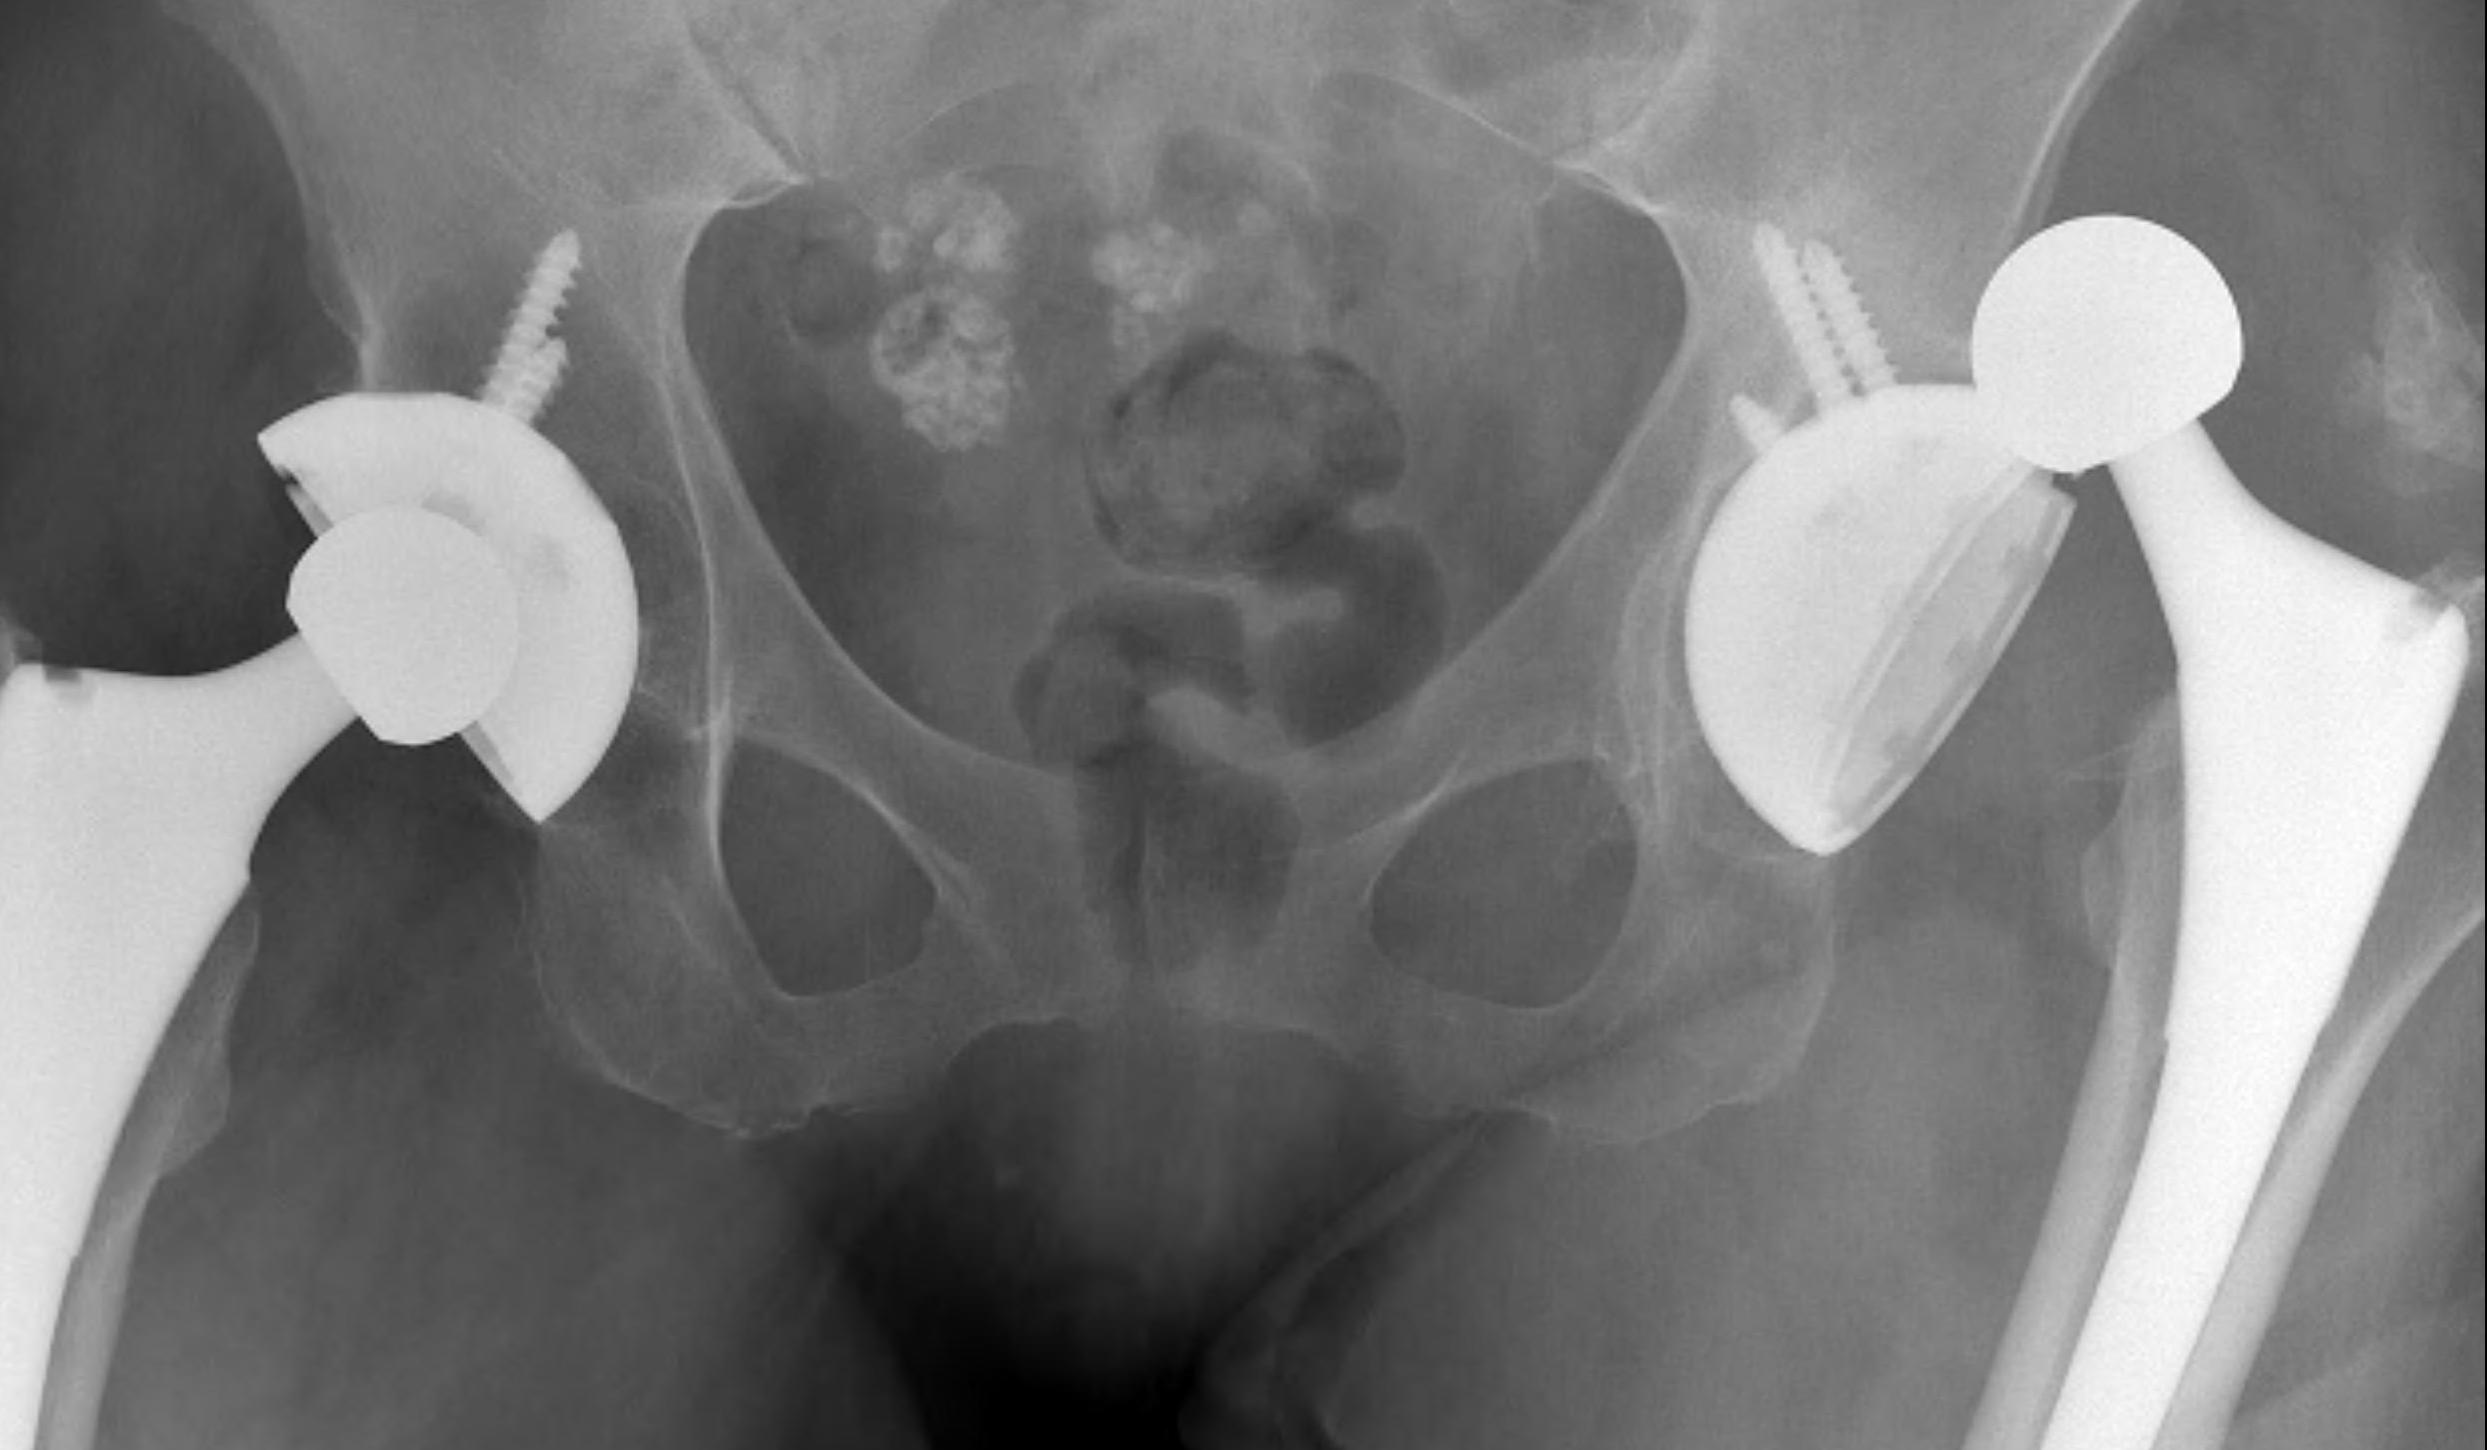

Positions

Posterior dislocation

- hip flexed, adducted, internally rotated

Anterior dislocation

- hip extended, adducted, externally rotation